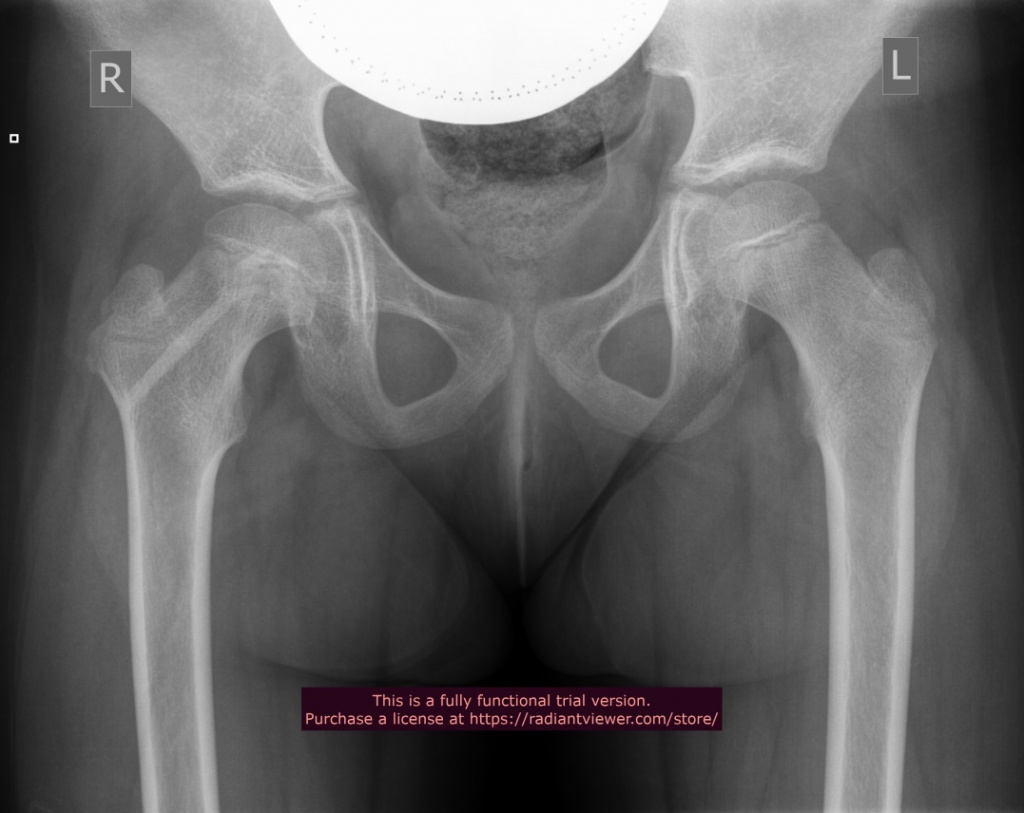

2015 год Пациентка Т., 7 лет |